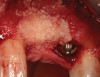

Figure 2  (Case 1) Condition of implant at surgical exposure.

Figure 2

Figure 3  (Case 1) Removal of implant was accomplished using piezo-surgery in order to maintain the lingual plate. Note that trephines are not recommended for this procedure.

Figure 3

Figure 4  (Case 1) Implant removed and lingual bone maintained to receive augmentation.

Figure 4